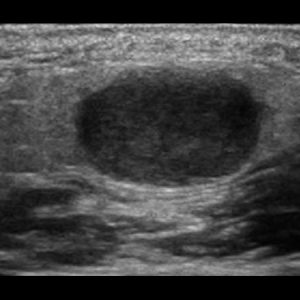

Bệnh Sjögren

Lượt xem: 201» 16-01-2021 -

Bệnh Sjögren

Lượt xem: 152» 16-01-2021 -

Bệnh Sjögren

Lượt xem: 162» 16-01-2021 -

Bệnh Sjögren

Lượt xem: 163» 16-01-2021 -

Viêm tuyến nước bọt

Lượt xem: 168» 16-01-2021 -

Viêm tuyến nước bọt

Lượt xem: 173» 16-01-2021